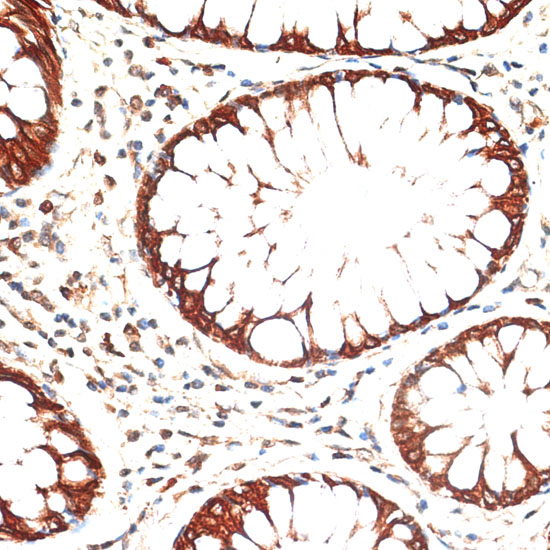

Immunohistochemistry of paraffin-embedded human colon carcinoma using KRT13 at dilution of 1:100 (40x lens).